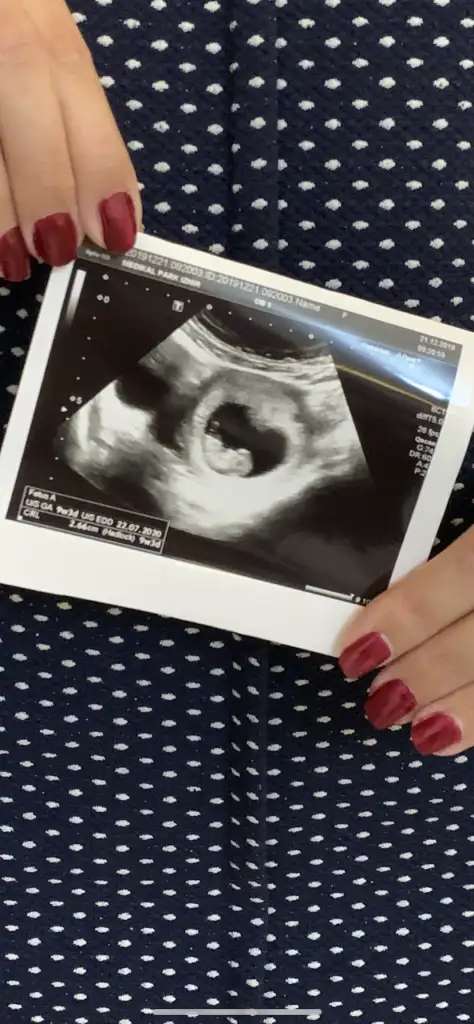

Merhaba belli oldu cinsiyetimiz gerçekten kızmış dr dan önce bildiniz helal olsun .Teşekkür ederim .Kardeşim çok sevindi kız istiyordu.Buna göre kız

Yaaa saglıkla gelsin anketimi oylarsanız sevinirimMerhaba belli oldu cinsiyetimiz gerçekten kızmış dr dan önce bildiniz helal olsun .Teşekkür ederim .Kardeşim çok sevindi kız istiyordu.

11 haftalık sizce ne ?Erkek gibi

Benim belli oldu 13.haftada dr bacak arasi bos k8z dediErkek gibi

Saglıkla gelsin 13 haftada çok erken tabi bazen değişebilir belkide değişmez 14-15 hatta 16 haftanızı degerlendirinBenim belli oldu 13.haftada dr bacak arasi bos k8z dedi